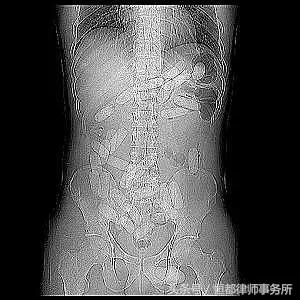

3.人体藏毒。一些马仔为了逃避公安机关的检查还会冒着巨大的生命危险采用体内藏毒方式运输*品毒**,这些*品毒**往往会先利用塑料袋将*品毒**粉末裹成小香肠形状,然后由藏毒者整个吞入体内,或者塞进肛门阴道等部位进行运输,到达目的地后再排出体外。